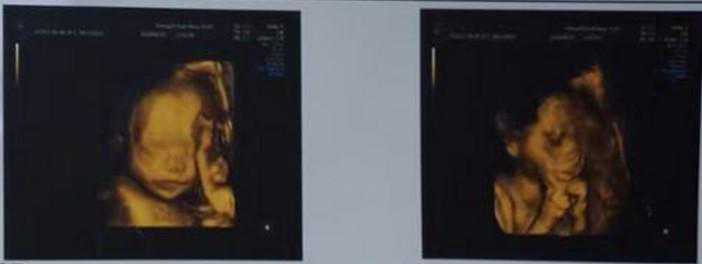

一路走到移植,到第十四天血值才318,怕生化,内心准备要放弃,还是做了一超,却意外发现双胎,真的是意外之喜,这心情起起落落的,之前毛毛躁躁的脾气,到现在都快磨圆了。

超声所见子宫前位,子宫形态正常,表面光滑,大小52x54x66,孕囊1大小约12x7,内见胎芽少许,其内可见胎心搏动。孕囊2大小27x7,其内未见卵黄囊及原始心管搏动。

超声提示,宫内早孕(双胎,双绒双羊)。

坯胎1存活,坯胎2目前未见胎芽及胎心搏动。

有一个宝宝有胎心,但还有一个宝宝暂时没有看到胎心,又开始忐忑不安起来,问大家说是这个情况还早,让安心静养,希望宝宝胎心快快的长上去。

再超胎心、胎芽都有了,越往后走越是担心。

11月23日诞下双男宝,一个四斤七两,一个五斤二两。